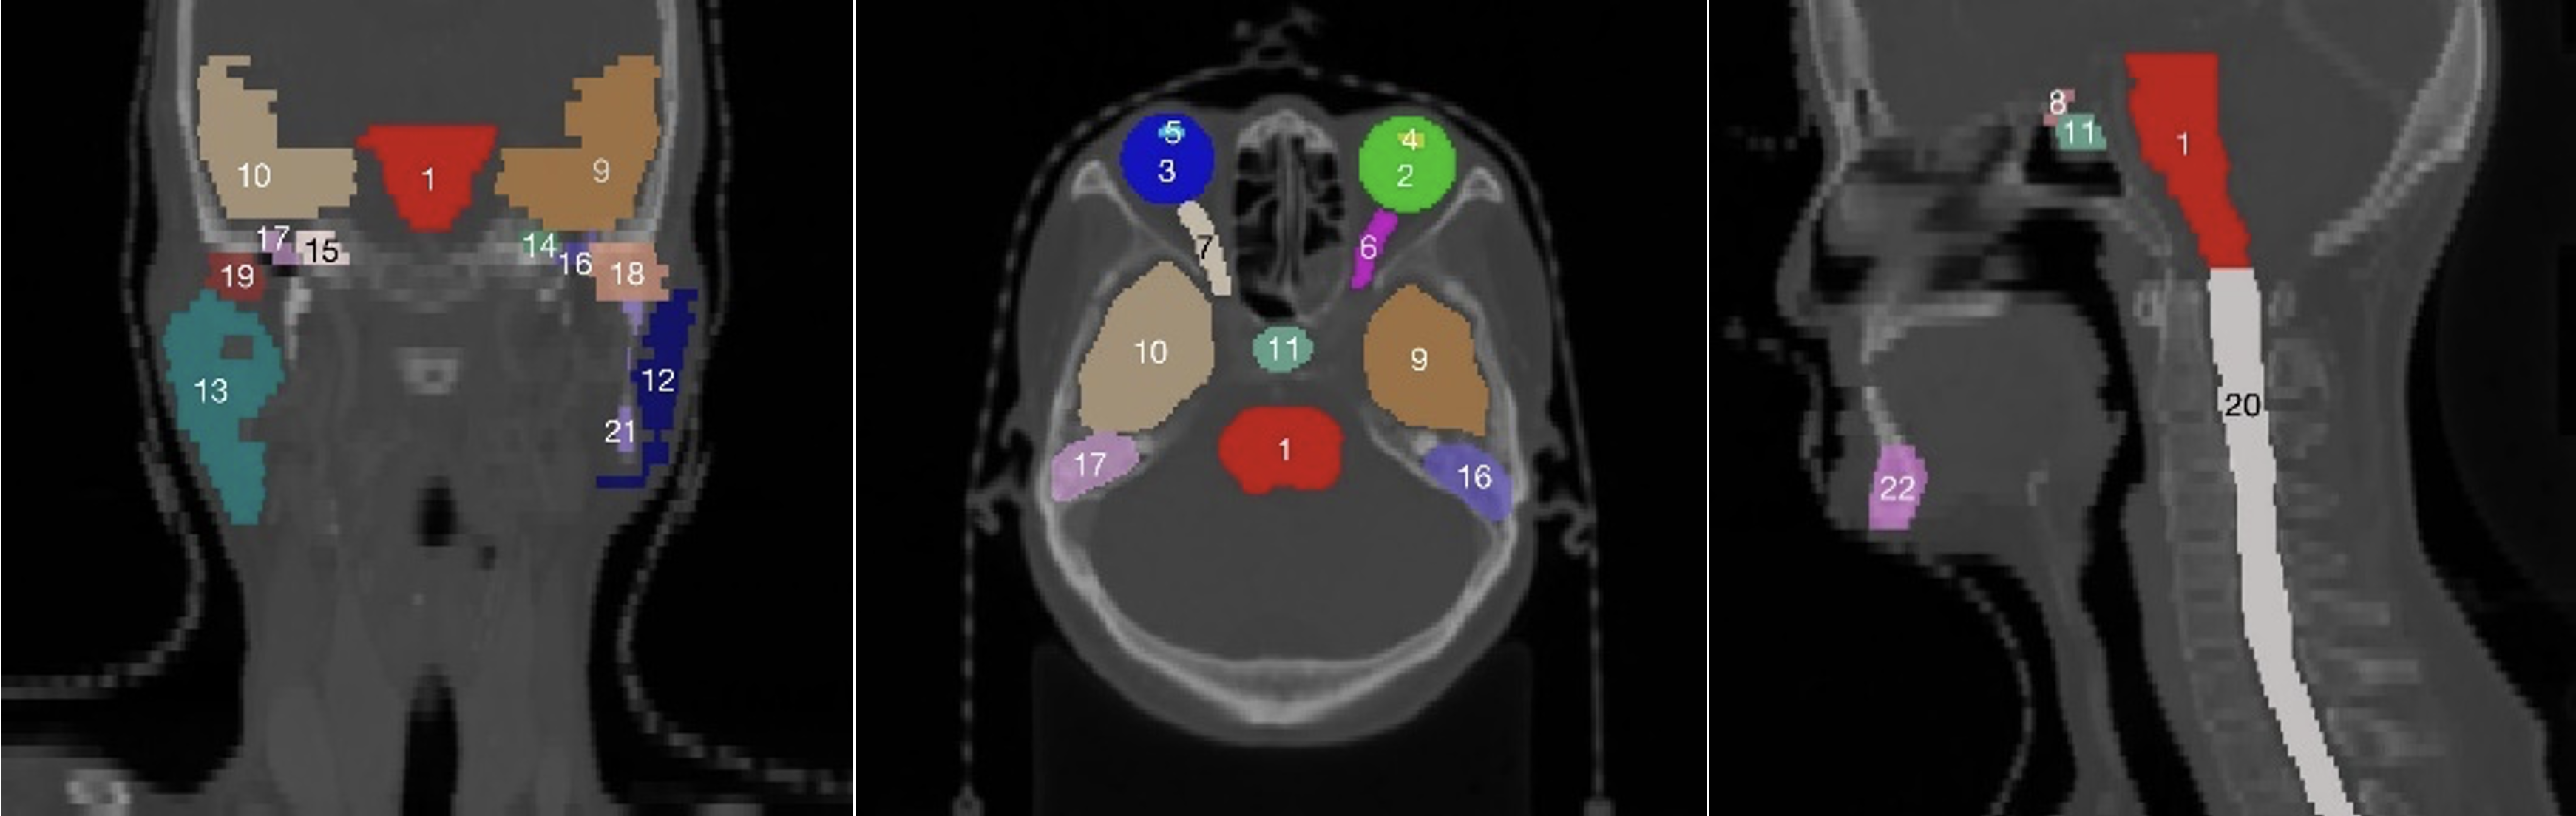

Using data-driven feature extraction approach and end-to-end training, the methods based on deep learning (DL) have been widely studied in the fields of image classification [21], object detection [22] and image segmentation [23, 24], image fusion [25], image registration [26], etc. The segmentation method based on deep learning has become a mainstream method in the field of medical image processing. However, there are two main difficulties in multi-organ deep learning segmentation tasks. First, as shown in the head and neck in Fig. 1, the abdomen in Fig. 2, the chest in Fig. 3, and the statistics of the multi-organ size in each part in Fig. 4, there are very large differences between the organs sizes, and the serious imbalances of different organs sizes will lead to a poor segmentation performance of the trained segmentation network for small organs. Second, due to the imaging principle of CT technology and the complex anatomical structure of the human body, the contrast between organs and their surrounding tissues is often low, which leads to the inaccurate segmentation of organ boundaries by segmentation networks. Therefore, it has become a new hot research topic to develop deep multi-organ segmentation methods that can accurately segment small and large organs at the same time.

The current multi-organ segmentation method is more effective in solving the segmentation of large organs and organs with standard contours, such as the brainstem and mandible in the head and neck; the left and right lungs and heart in the chest; and the liver, spleen, and stomach in the abdomen. Moreover, the DSC of various methods can basically reach 0.8 or higher, while for small organs, such as the optical chiasm in the head and neck (see Fig. 1(8)), the left and right optic nerves (see Fig. 1(6 and 7)), the DSC can only reach about 0.7; irregular organs such as the pancreas in the abdomen (Fig. 2(4)), and long striped organs such as the spinal cord (Fig. 2(6)), the segmentation results are also not very satisfactory. The future research direction is to enhance the segmentation accuracy of these types of organs using more advanced automatic segmentation frameworks.